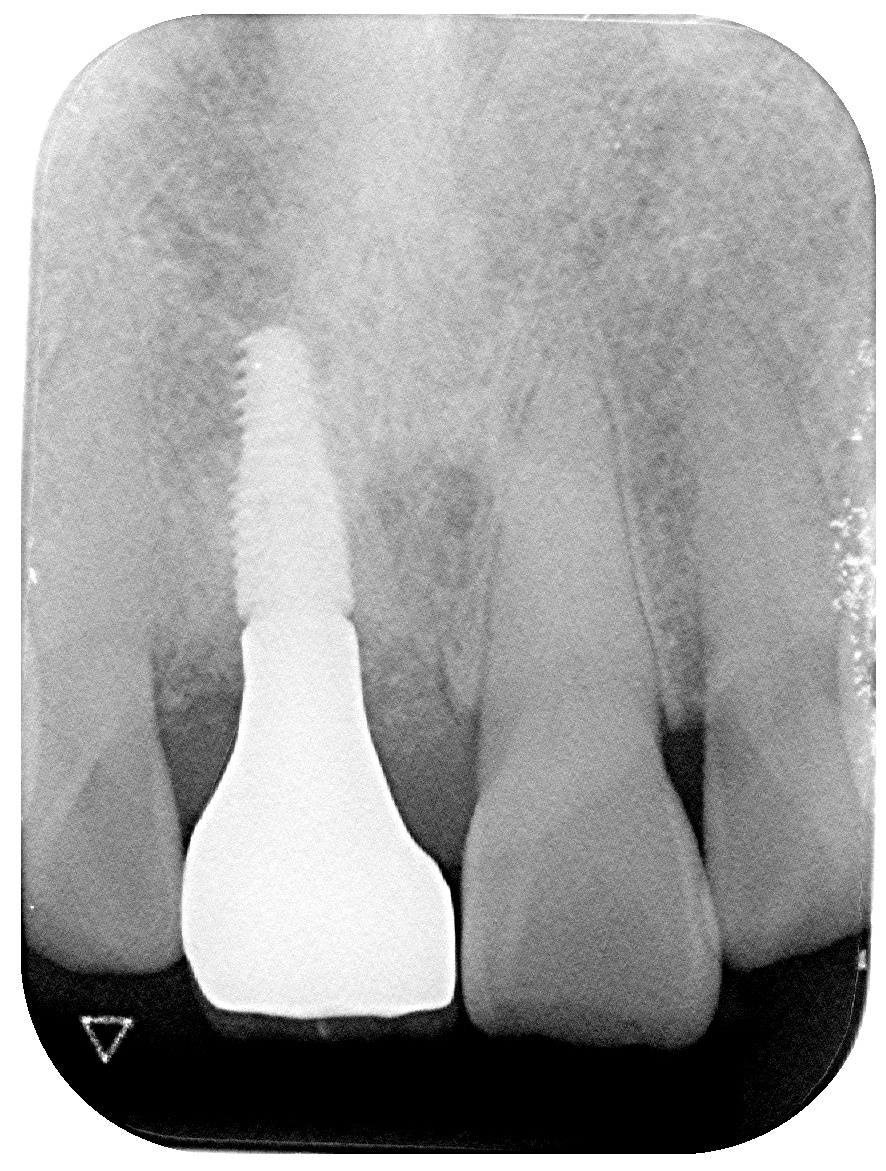

患者様に状態を丁寧にご説明し、十分なご理解とご同意をいただいた上で、

抜歯即時インプラント治療を行いました。

抜歯と同時にインプラントを埋入することで、

骨の吸収を最小限に抑えながら見た目と機能を早期に回復できます。